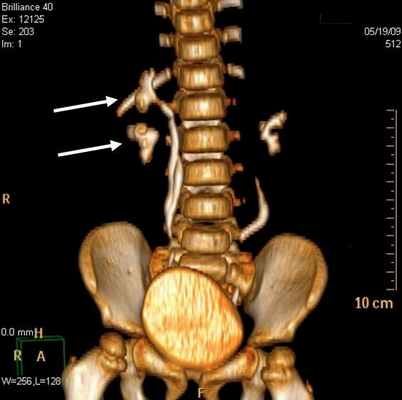

Стеноз устья мочеточника на МСКТ выявлен в 29 (78,4%) наблюдениях (рис 4). Данная патология у 17 детей была с обеих сторон, а 3 наблюдениях этот порок сочетался с уретероцеле и эктопией устьев мочеточника.

Рис 4. Стеноз устья мочеточника. Трехмерная реконструкция. Больной К., 6 лет. Деформирование мочеточников и сужение устья мочеточников